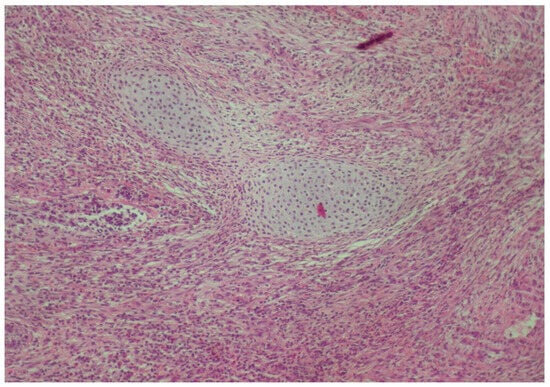

2. Case Presentation